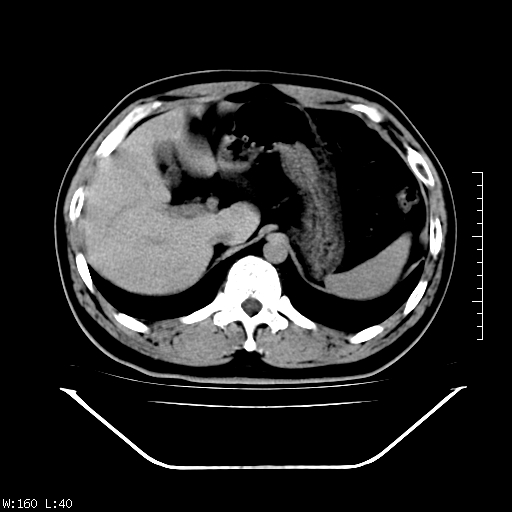

标题: CT25310:男,38,右上腹偶有隐痛,未做肠道准备。 [打印本页]

标题: CT25310:男,38,右上腹偶有隐痛,未做肠道准备。

慢性胆囊炎,胆结石。

慢性胆囊炎。